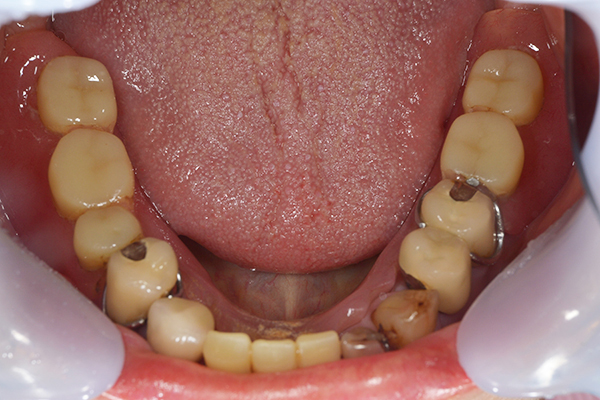

入れ歯を入れた状態のお口の中の写真です。バネも極力目立たないように作成しています。

お口の中に入れた状態です。 非常に見た目もよい出来となりました。 バネがみえないと見栄えが全然ちがいます。